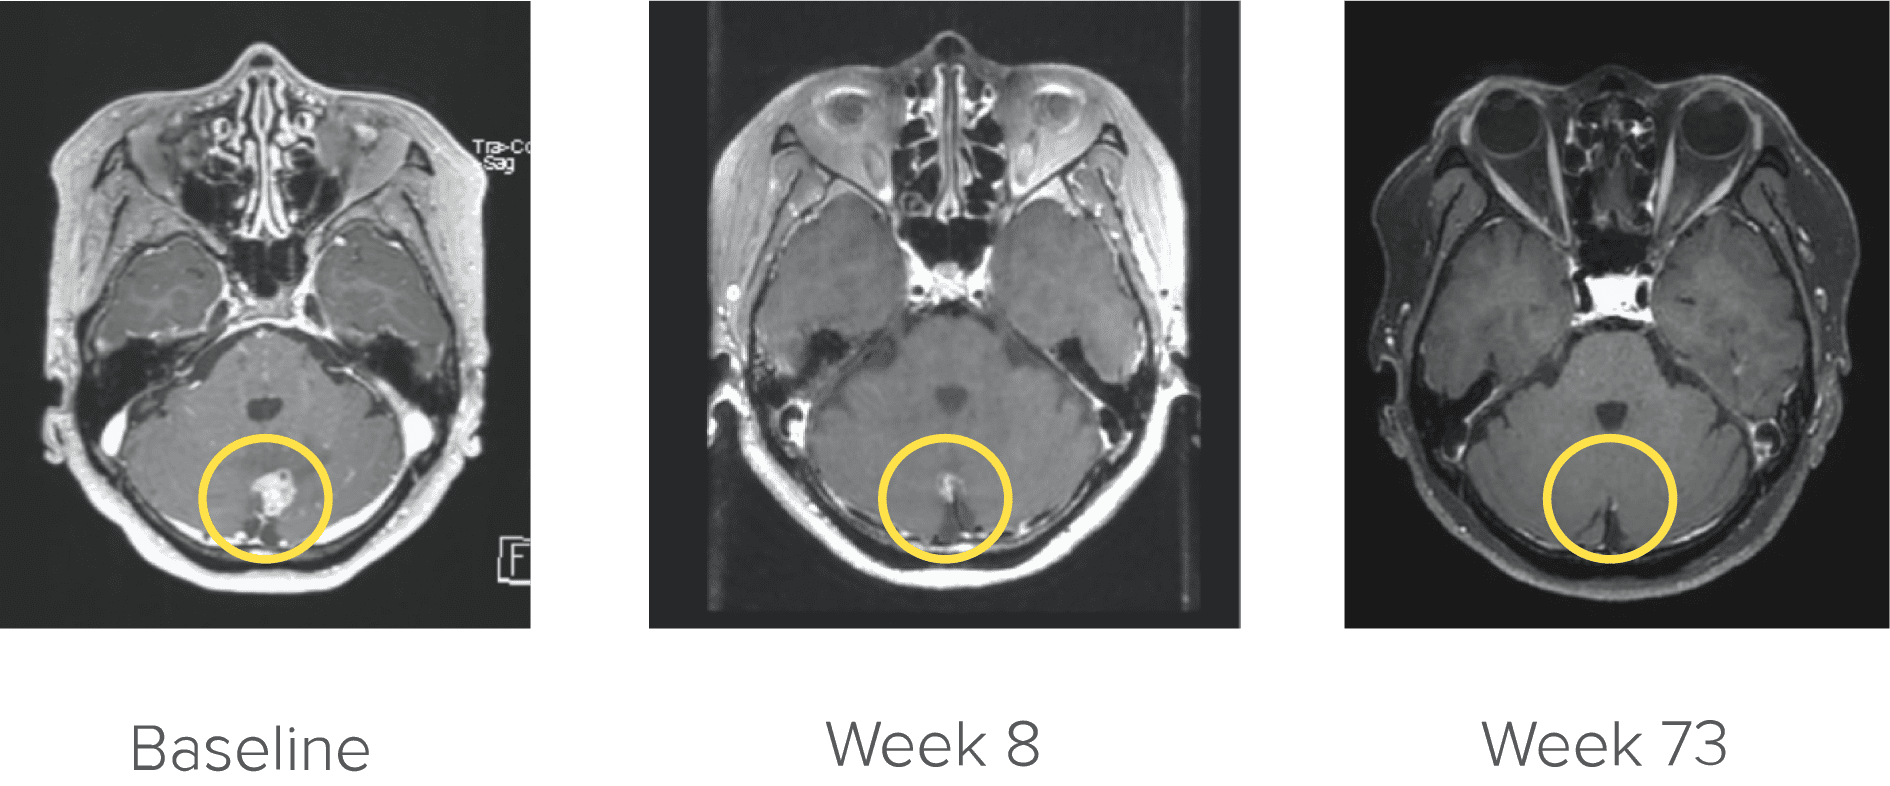

CNS ACTIVITY1

Brain metastases at baseline (n=10)‡

70%

of previously platinum-treated patients with measurable disease had a response

71%

DoR

≥6 months

‡No patients received radiation therapy (RT) to the brain within 2 months prior to study entry.

Courtesy of Dr. Kim. Image is from a patient in the ARROW trial who achieved complete CNS response. Image is for illustrative purposes only; individual results may vary. According to the protocol, images were to be performed every 8 weeks (±7 days).4